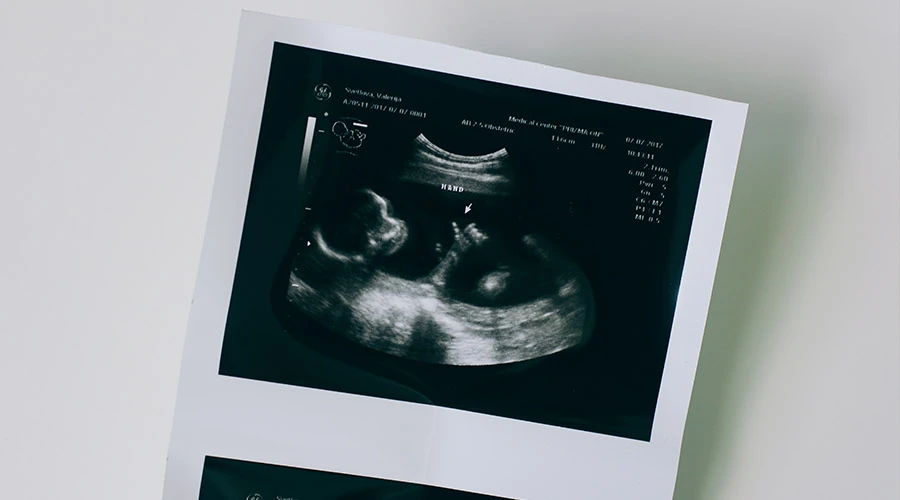

El experimento consistió en hacer que 100 mujeres embarazadas tomen cápsulas de zanahoria y col rizada, para que al poco tiempo se les realicen ecografías 4D que permitan observar las expresiones faciales y reacciones de sus bebés.

Según el estudio, "los fetos expuestos al sabor de zanahoria mostraron más respuestas de 'cara de risa', mientras que los expuestos al sabor de col rizada mostraron más respuestas de 'cara de llanto'".